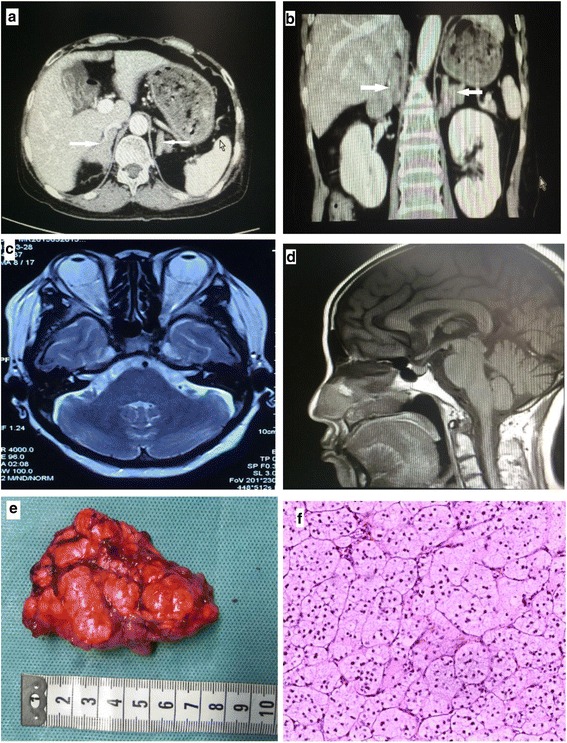

Complete blood count, urine analysis, and renal and liver function tests were all normal. A biochemical evaluation revealed elevated 24-hour urinary free cortisol (UFC) 306.8 μg/24 hours (reference range 3.5 to 45 μg/24 hours), elevated cortisol level, and suppressed ACTH level with loss of their normal diurnal rhythm. Her cortisol level was 634 ug/L at 8 a.m., 621 ug/L at 4 p.m., and 521 ug/L at 0 a.m. (reference range 62 to 194 ug/L), while her ACTH level was always < 1 ng/L (reference range 7.2 to 63.6 ng/L). Serum cortisol remained unsuppressed after 1 mg overnight and high-dose dexamethasone suppression tests (at 624 ug/L and 607 ug/L, respectively). Serum thyroid function tests were normal; anti-thyrotropin receptor antibody (TRAb), anti-thyroid peroxidase (TPOAb), and anti-thyroglobulin antibodies (TGAb) were negative. Plasma potassium was 2.2~3.0 mmol/L. Glycated hemoglobin (HbA1c) was 8.7%. Serum androgen, aldosterone/renin activity ratio, and 24-hour urinary catecholamines were all in the normal range. Glucagon, luteinizing hormone-releasing hormone (LHRH), mixed meal, postural, metoclopramide, and vasopressin tests were performed in order to evaluate aberrant hormonal responses. Results were positive for vasopressin and upright posture test. Computed tomography (CT) imaging of her adrenal glands revealed bilateral multiple lobular masses (Fig. 1a, b); magnetic resonance imaging (MRI) of her orbits indicated bilateral exophthalmos with hypertrophy of the retro-orbital fat (Fig. 1c); MRI of her pituitary was normal (Fig. 1d). Diagnosis of PBMAH was made and our patient underwent bilateral laparoscopic adrenalectomy. Gross pathological examination of adrenal glands showed each gland contained several nodules (Fig. 1e). Pathological findings were consistent with PBMAH: multinodular glands with homogenous, golden-yellow-colored nodules. Nodules contained predominantly fascicular cells (Fig. 1f). After surgery, her plasma cortisol and ACTH at 8 a.m. were 6.06 ug/L and 1.87 ng/L respectively, indicating a successful surgery. Hydrocortisone supplementation was given as well, as she was started on metformin for diabetes. At 6-month follow-up, her blood glucose levels were well controlled and her blood pressure was 120/80 mmHg without use of any antihypertensive medication. The exophthalmos improved markedly after the surgery.

Fig. 1.

Clinical features of the patient with primary bilateral macronodular adrenal hyperplasia. Computed tomography scan of adrenal glands showed massive enlargement of the adrenal glands and multiple nodules (as shown by arrows) (a, b). Magnetic resonance imaging of the orbital showed bilateral exophthalmos (c). MRI of the pituitary gland was normal (d).Gross pathology of the resected left adrenal gland with nodules of various sizes (e). Histological view of resected adrenal tissue showing the presence of large cortical cells shown by hematoxylin and eosin stain at magnification × 100 (f)